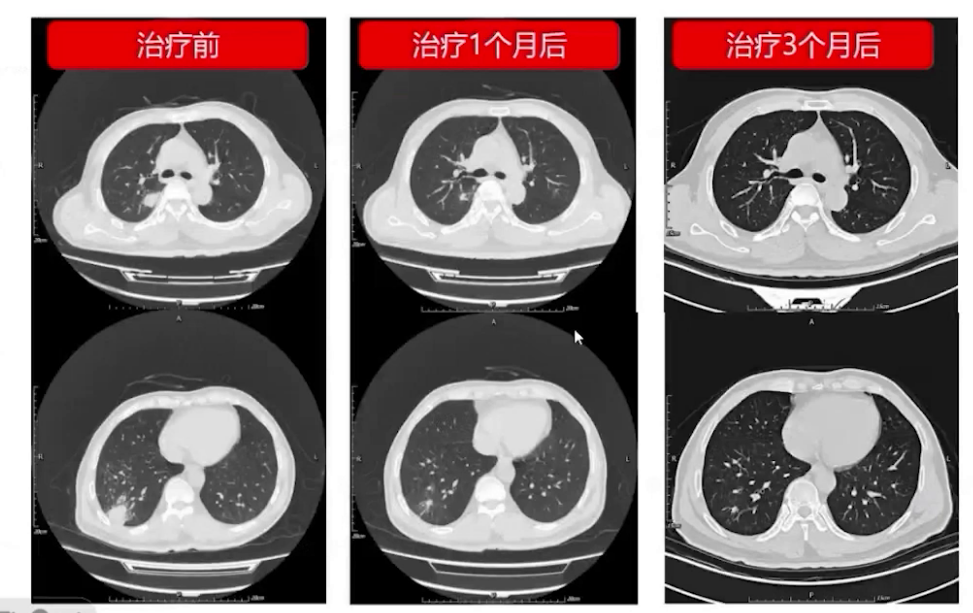

给予伏立康唑片200mg bid抗真菌治疗。

患者出院后症状改善,右侧肢体肌力恢复正常,定期监测伏立康唑血药浓度正常,随访胸部CT及头颅MRI显示病灶持续缩小。